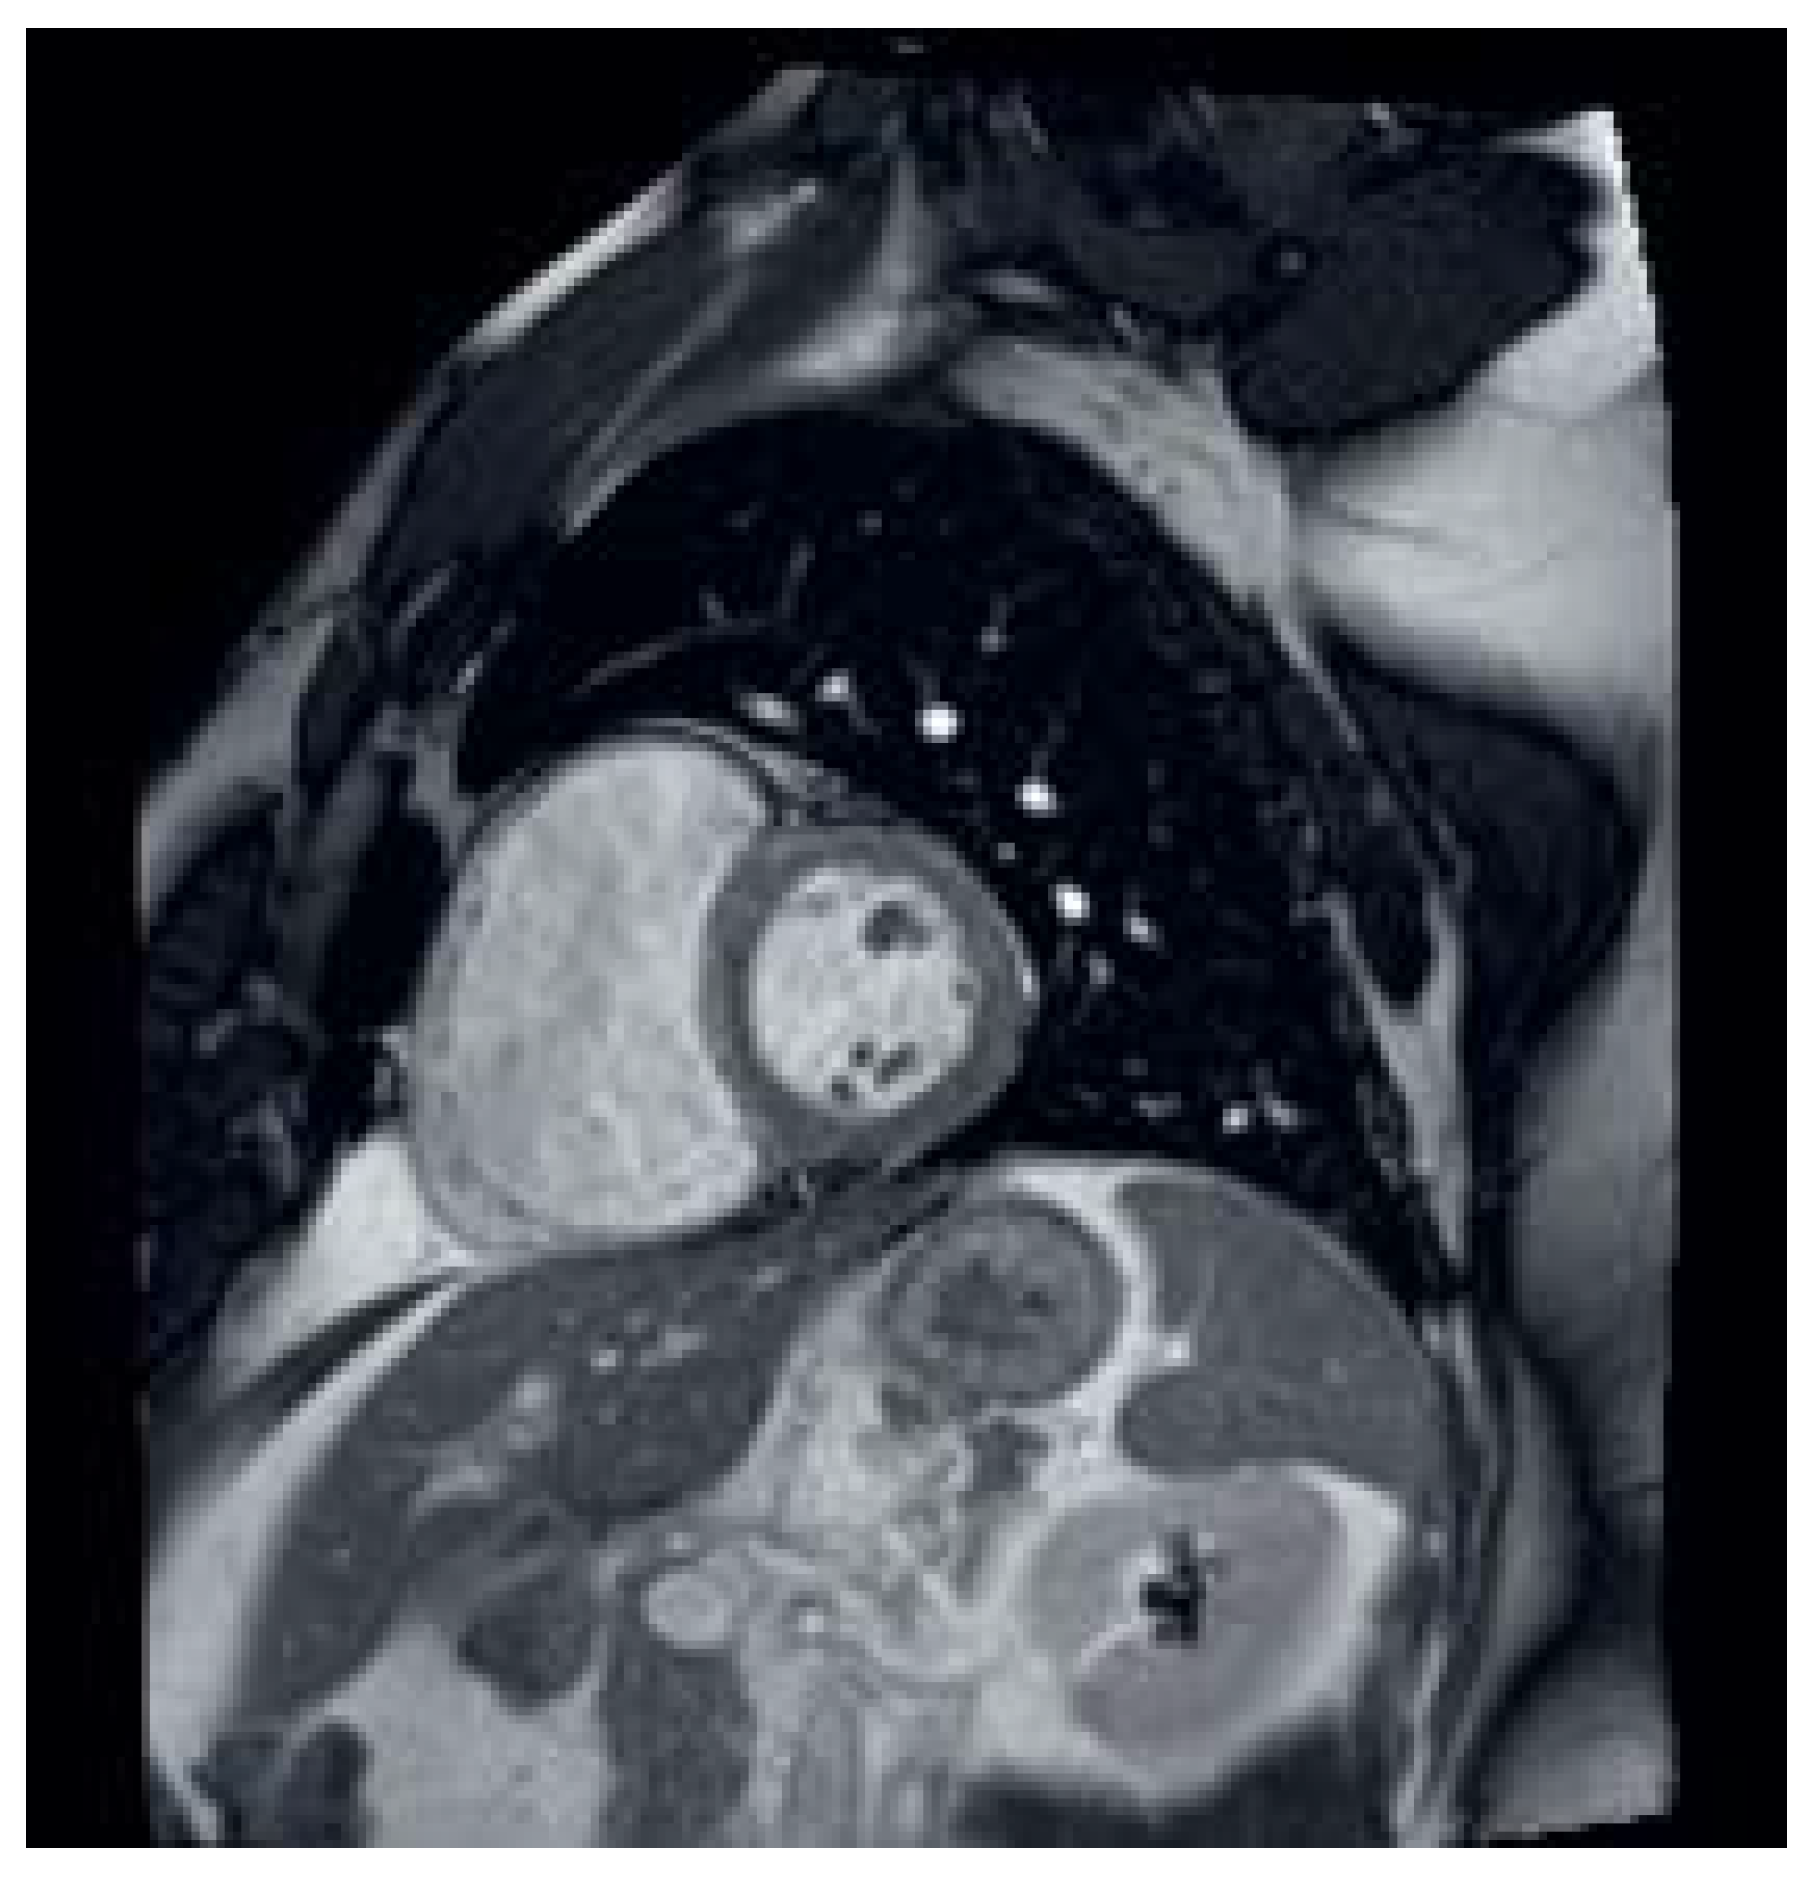

Sinus Venosus Atrial Septal Defect with Partial Anomalous Pulmonary Vein Return †

Case description